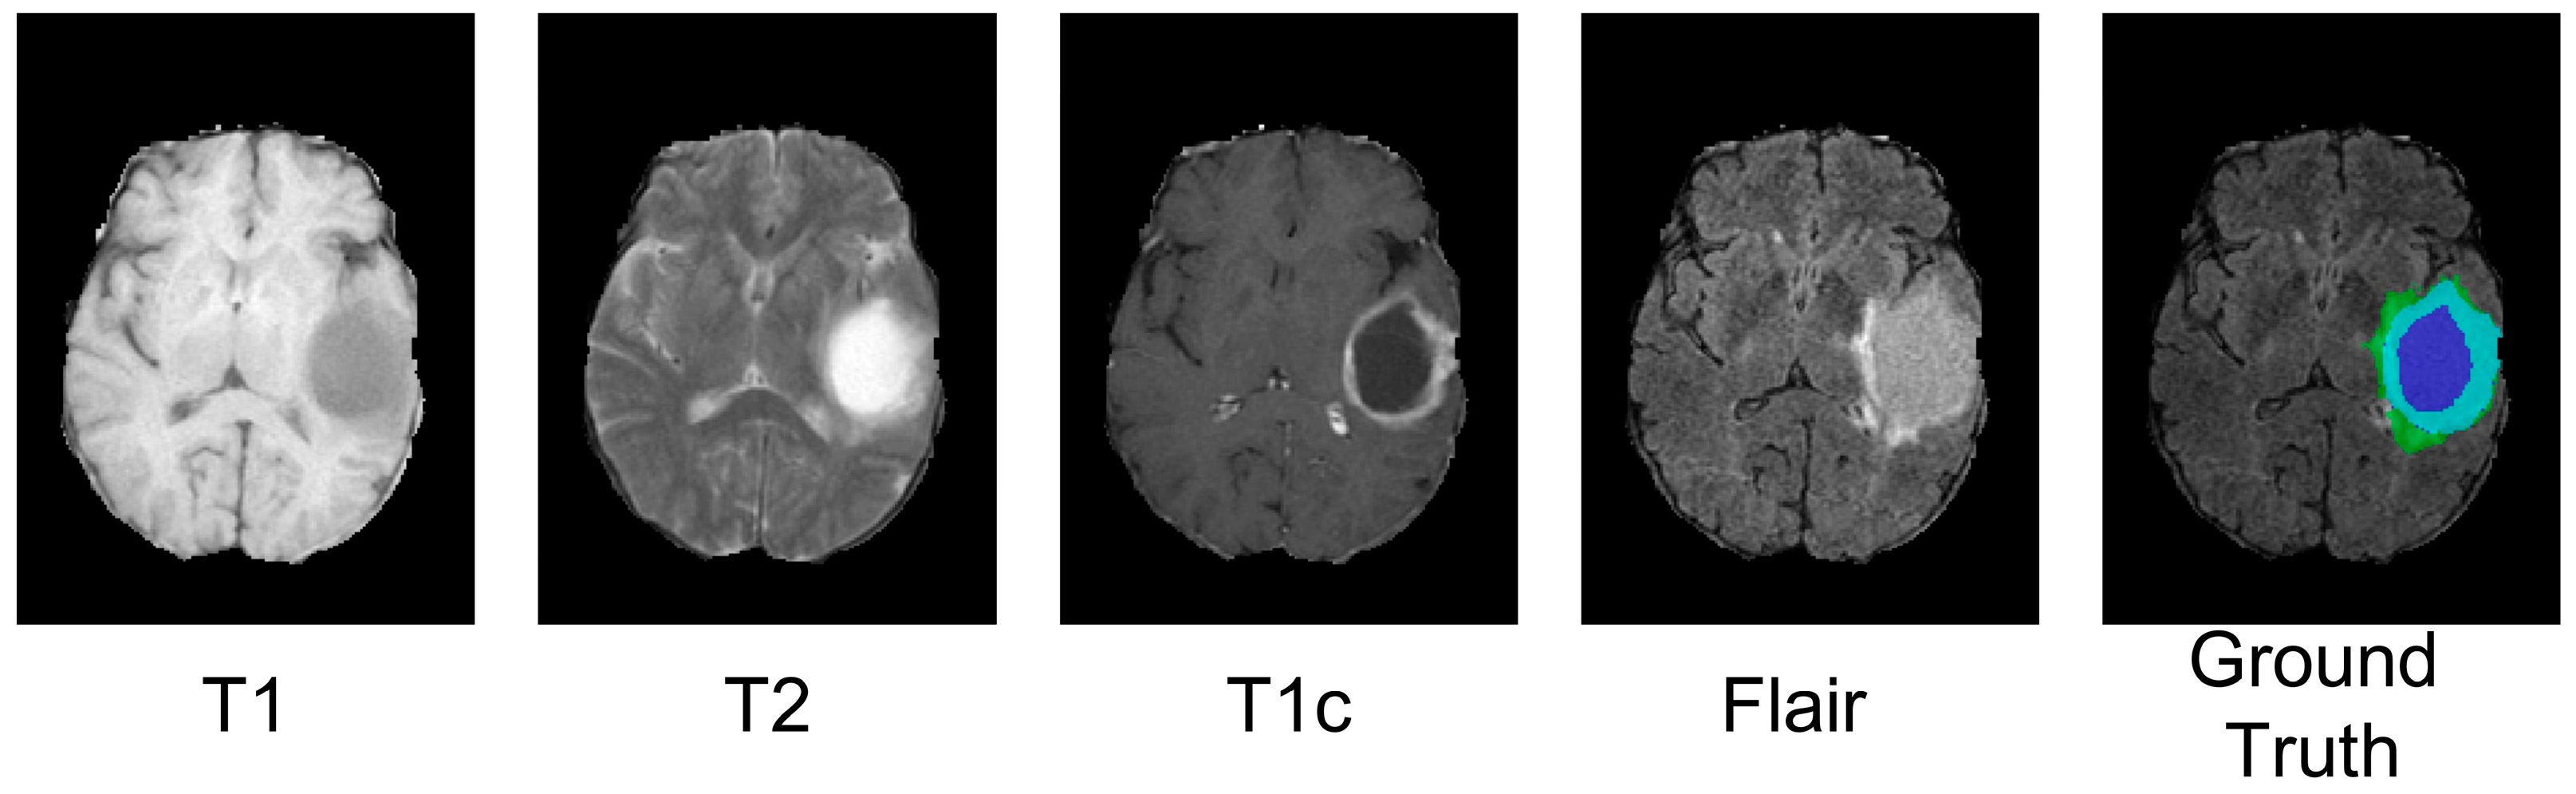

4.3. Analysis of the Bad Tumor Segmentation Results

| Cases | DSC | |||

|---|---|---|---|---|

| ET | TC | WT | AVG | |

| (a) BraTS2021_00493 | 0.885 | 0.924 | 0.270 | 0.693 |

| (b) BraTS2021_00494 | 0.964 | 0.990 | 0.730 | 0.895 |

| (c) BraTS2021_01666 | 0 | 0.738 | 0.916 | 0.551 |

| (d) BraTS2021_01179 | 1.000 | 0 | 0.769 | 0.590 |

| (e) BraTS2021_01293 | 0.541 | 0.929 | 0.874 | 0.781 |